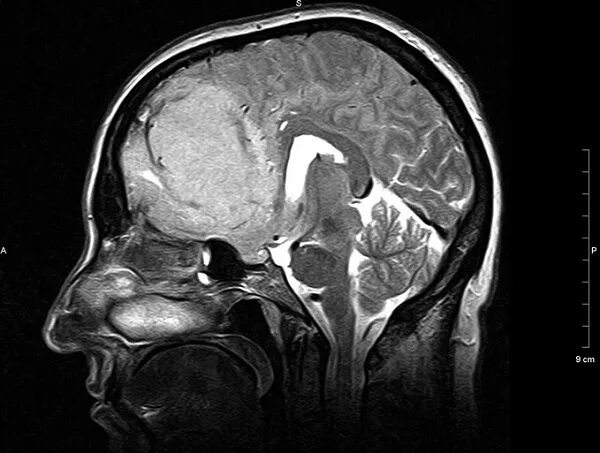

Мрт головного мозга мосто мозжечкового угла